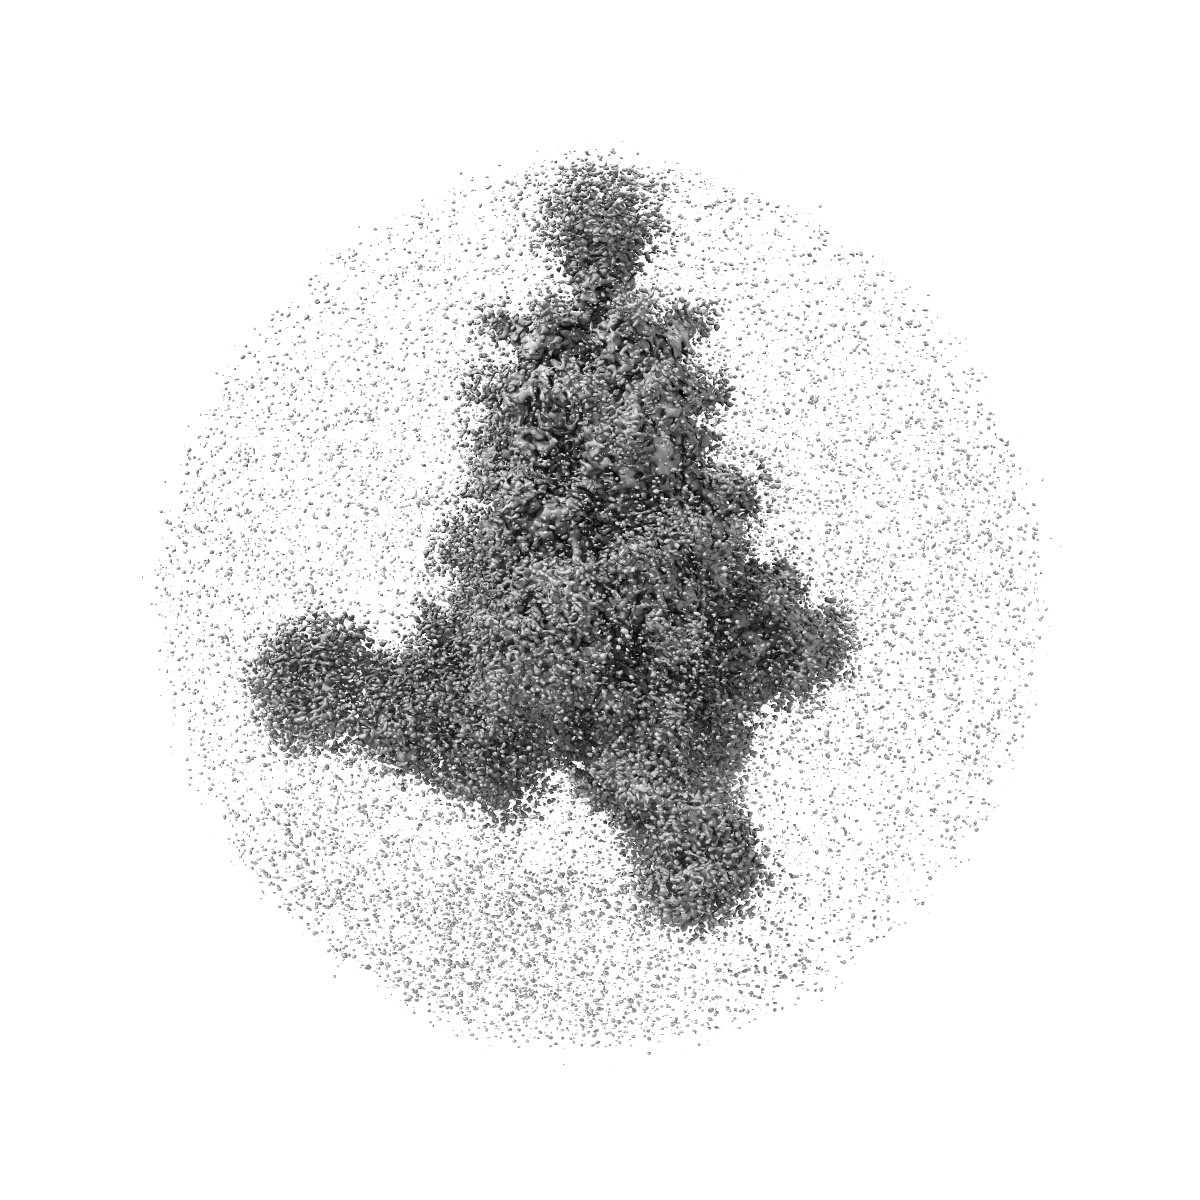

Cryo-EM structure of SARS-CoV-2 Omicron spike protein (S-6P-RRAR) in complex with S309 fab

Sample: Cryo-EM structure of SARS-CoV-2 Omicron spike protein in complex with S309 fab